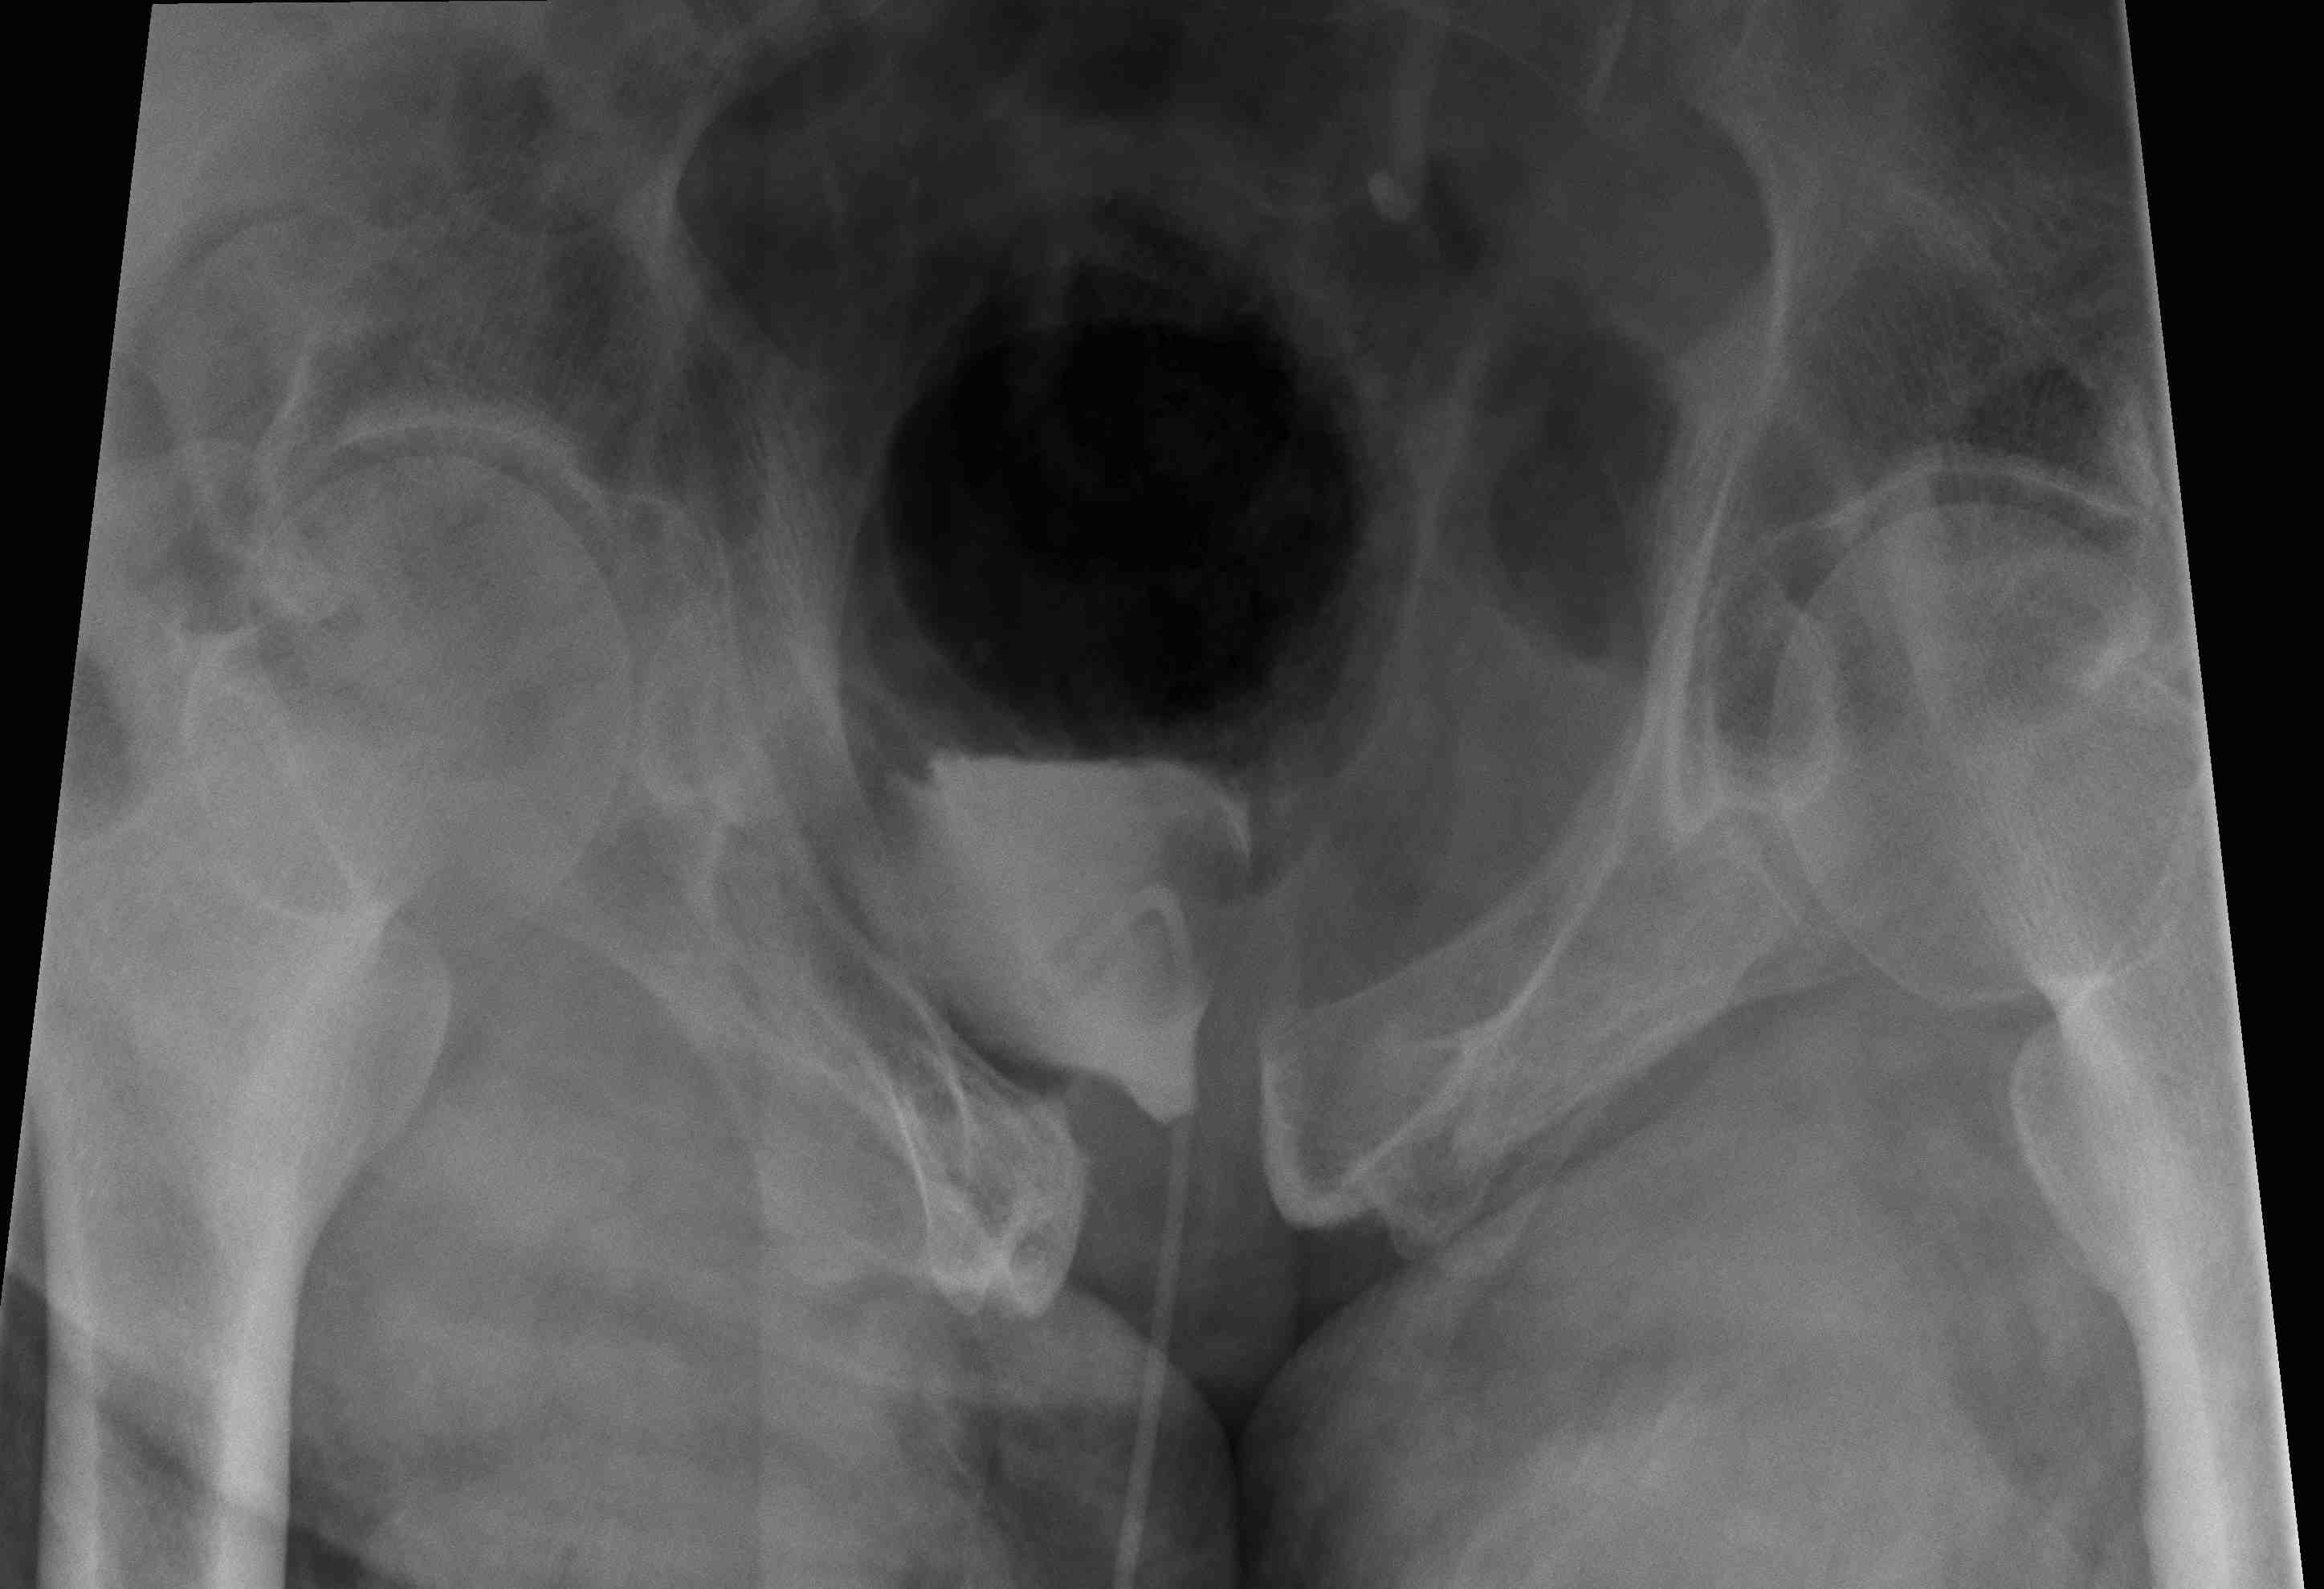

APC-3

APC 3Complete SI joint disruption

Pubic diastasis > 5 cm with complete SI joint disruption